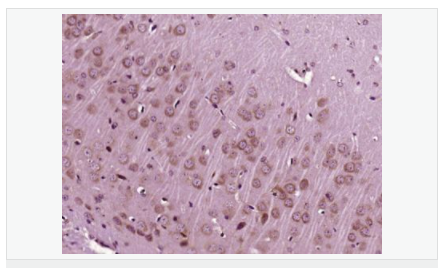

| 產品應用 | WB=1:500-2000 ELISA=1:5000-10000 IP=1:20-100 IHC-P=1:100-500 IHC-F=1:100-500 IF=1:100-500 (石蠟切片需做抗原修復) not yet tested in other applications. optimal dilutions/concentrations should be determined by the end user. |

| 英文名稱 | IGF 1 |

| 中文名稱 | 胰島素樣生長因子1抗體 |

| 別 名 | IBP1; IGF 1; IGF I; IGF-1;IGF IA; IGF IB; IGF1; IGFI; IGFIA; Insulin like growth factor 1 (somatomedin C); Full=Insulin-like growth factor I; Insulin Like Growth Factor 1; Insulin like growth factor IA; Insulin like growth factor IB; Mechano growth factor; MGF; Mechano growth factor; MGF; Somatomedia C; Somatomedin C; IGF1_HUMAN. |